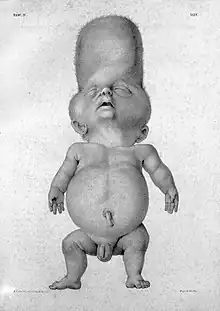

Thanatophoric dysplasia is a severe skeletal disorder characterized by a disproportionately small ribcage, extremely short limbs and folds of extra skin on the arms and legs.

Infants with this condition have disproportionately short arms and legs with extra folds of skin. Other signs of the disorder include a narrow chest, small ribs, underdeveloped lungs, and an enlarged head with a large forehead and prominent, wide-spaced eyes. Thanatophoric dysplasia is a lethal skeletal dysplasia divided into two subtypes. Type I is characterized by extreme rhizomelia, bowed long bones, narrow thorax, a relatively large head, normal trunk length and absent cloverleaf skull. The spine shows platyspondyly, the cranium has a short base, and, frequently, the foramen magnum is decreased in size. The forehead is prominent, and hypertelorism and a saddle nose may be present. Hands and feet are normal, but fingers are short. Type II is characterized by short, straight long bones and cloverleaf skull.[1] It presents with typical telephone-handle shaped long bones and H-shaped vertebrae.

Infants with type 1 thanatophoric dysplasia also have curved thigh bones, flattened bones of the spine (platyspondyly) and shortened thoracic ribs. Note: Prenatal ultra-sound images of the ribs sometimes appear asymmetrical when in fact they are not. In certain cases, this has caused a misdiagnosis of osteogenisis imperfecta (OI) type II.